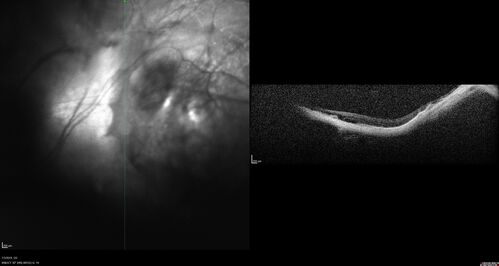

Staphyloma and Atrophy with Vitreoretinal traction

Only eye of patient with Albinism and decreasing vision now 5/200 in this 72 year old man. There is myopic tractional maculopathy. The patient also has albinism by history.

Myopic Staphyloma and Albinism